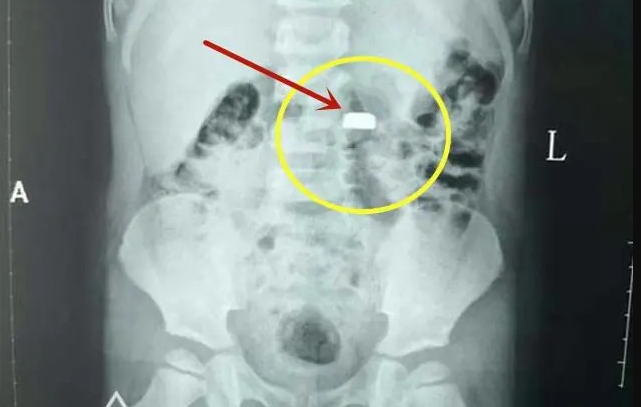

ส่งโรงพยาบาลด่วนที่สุด: แจ้งหมอทันทีว่าสงสัยว่าลูกกลืนถ่าน เพื่อรับการเอกซเรย์และส่องกล้องออกทันที